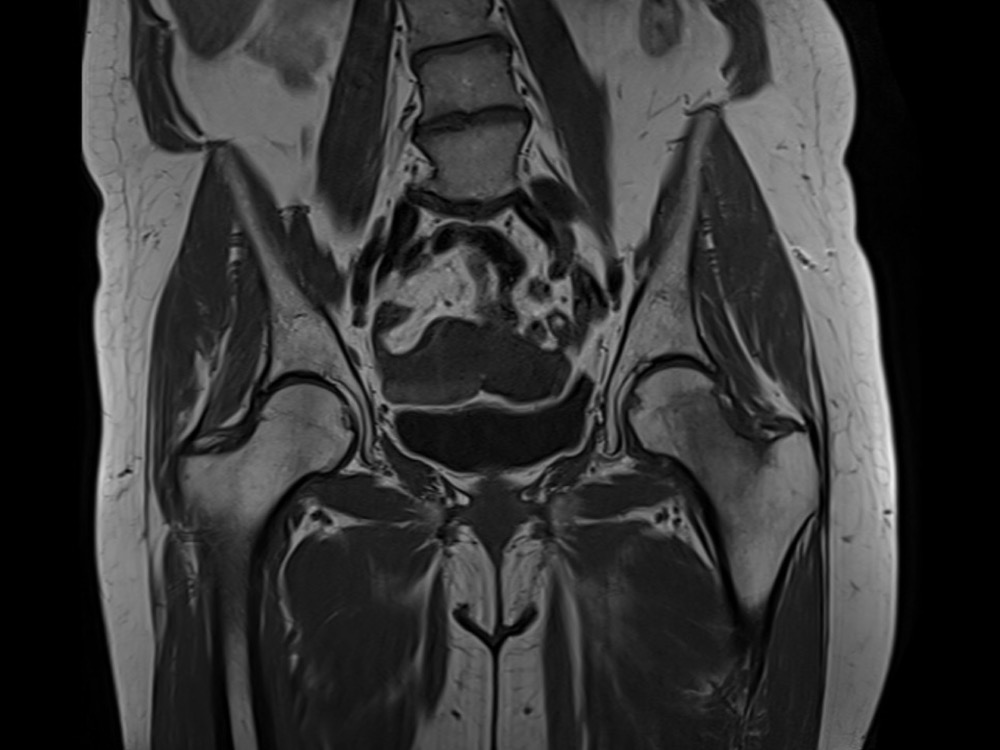

Douleurs de hanche

Linda Ouerd 06/11/2019